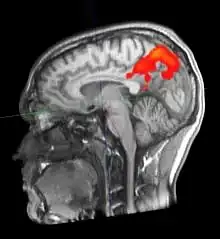

Durch fMRT-Aufnahmen ist es möglich, Durchblutungsänderungen von Hirnarealen sichtbar zu machen, die auf Stoffwechselvorgänge zurückgeführt werden, welche wiederum mit neuronaler Aktivität in Zusammenhang stehen. Hierbei macht man sich die unterschiedlichen magnetischen Eigenschaften von oxygeniertem und desoxygeniertem Blut zunutze (BOLD-Kontrast). Bei der Aktivierung von Kortexarealen kommt es zu einer Steigerung des Stoffwechsels, wodurch das aktivierte Areal mit einer überproportionalen Erhöhung des Blutflusses reagiert (sog. neurovaskuläre Kopplung). Dadurch erhöht sich die Konzentration von oxygeniertem (diamagnetischem) relativ zu desoxygeniertem (paramagnetischem) Hämoglobin. Über den intermolekularen Elektronendipol-Kerndipol-Relaxationsmechanismus bewirkt diese Konzentrationsänderung eine Veränderung der effektiven transversalen Relaxationszeit der beobachteten Wasserstoff-Kernspins und führt damit zu einer Signaländerung in der MRT. Um so Rückschlüsse auf den Ort einer neuronalen Aktivität zu ziehen, wird das Magnetresonanz-Signal des Gewebes zu zwei Zeitpunkten verglichen – z. B. im stimulierten oder Experimentalzustand einerseits sowie im Ruhe- oder Kontrollzustand andererseits. Die Aufnahmen können durch statistische Testverfahren miteinander verglichen und die statistisch signifikanten Unterschiede (die den stimulierten Arealen entsprechen) räumlich zugeordnet und dargestellt werden.

Bei einer Untersuchung des Gehirns zu Versuchszwecken kann dem Probanden im dritten Teilscan zum Beispiel ein wiederholter Reiz präsentiert werden. Häufig wird der Reiz mit einer Aufgabe für den Probanden verknüpft, etwa der Aufforderung, bei jedem gezeigten Objekt X eine Taste zu drücken. Den meisten Versuchen gemein ist die häufige Wiederholung der Aufgabe. So kann dann durch statistische Verfahren ein Vergleich aufgezeichneter Daten aus der Reizphase mit denen aus der Ruhephase stattfinden. Der hieraus berechnete Unterschied wird dann in Falschfarben auf den zuvor durchgeführten anatomischen MR-Scan projiziert.